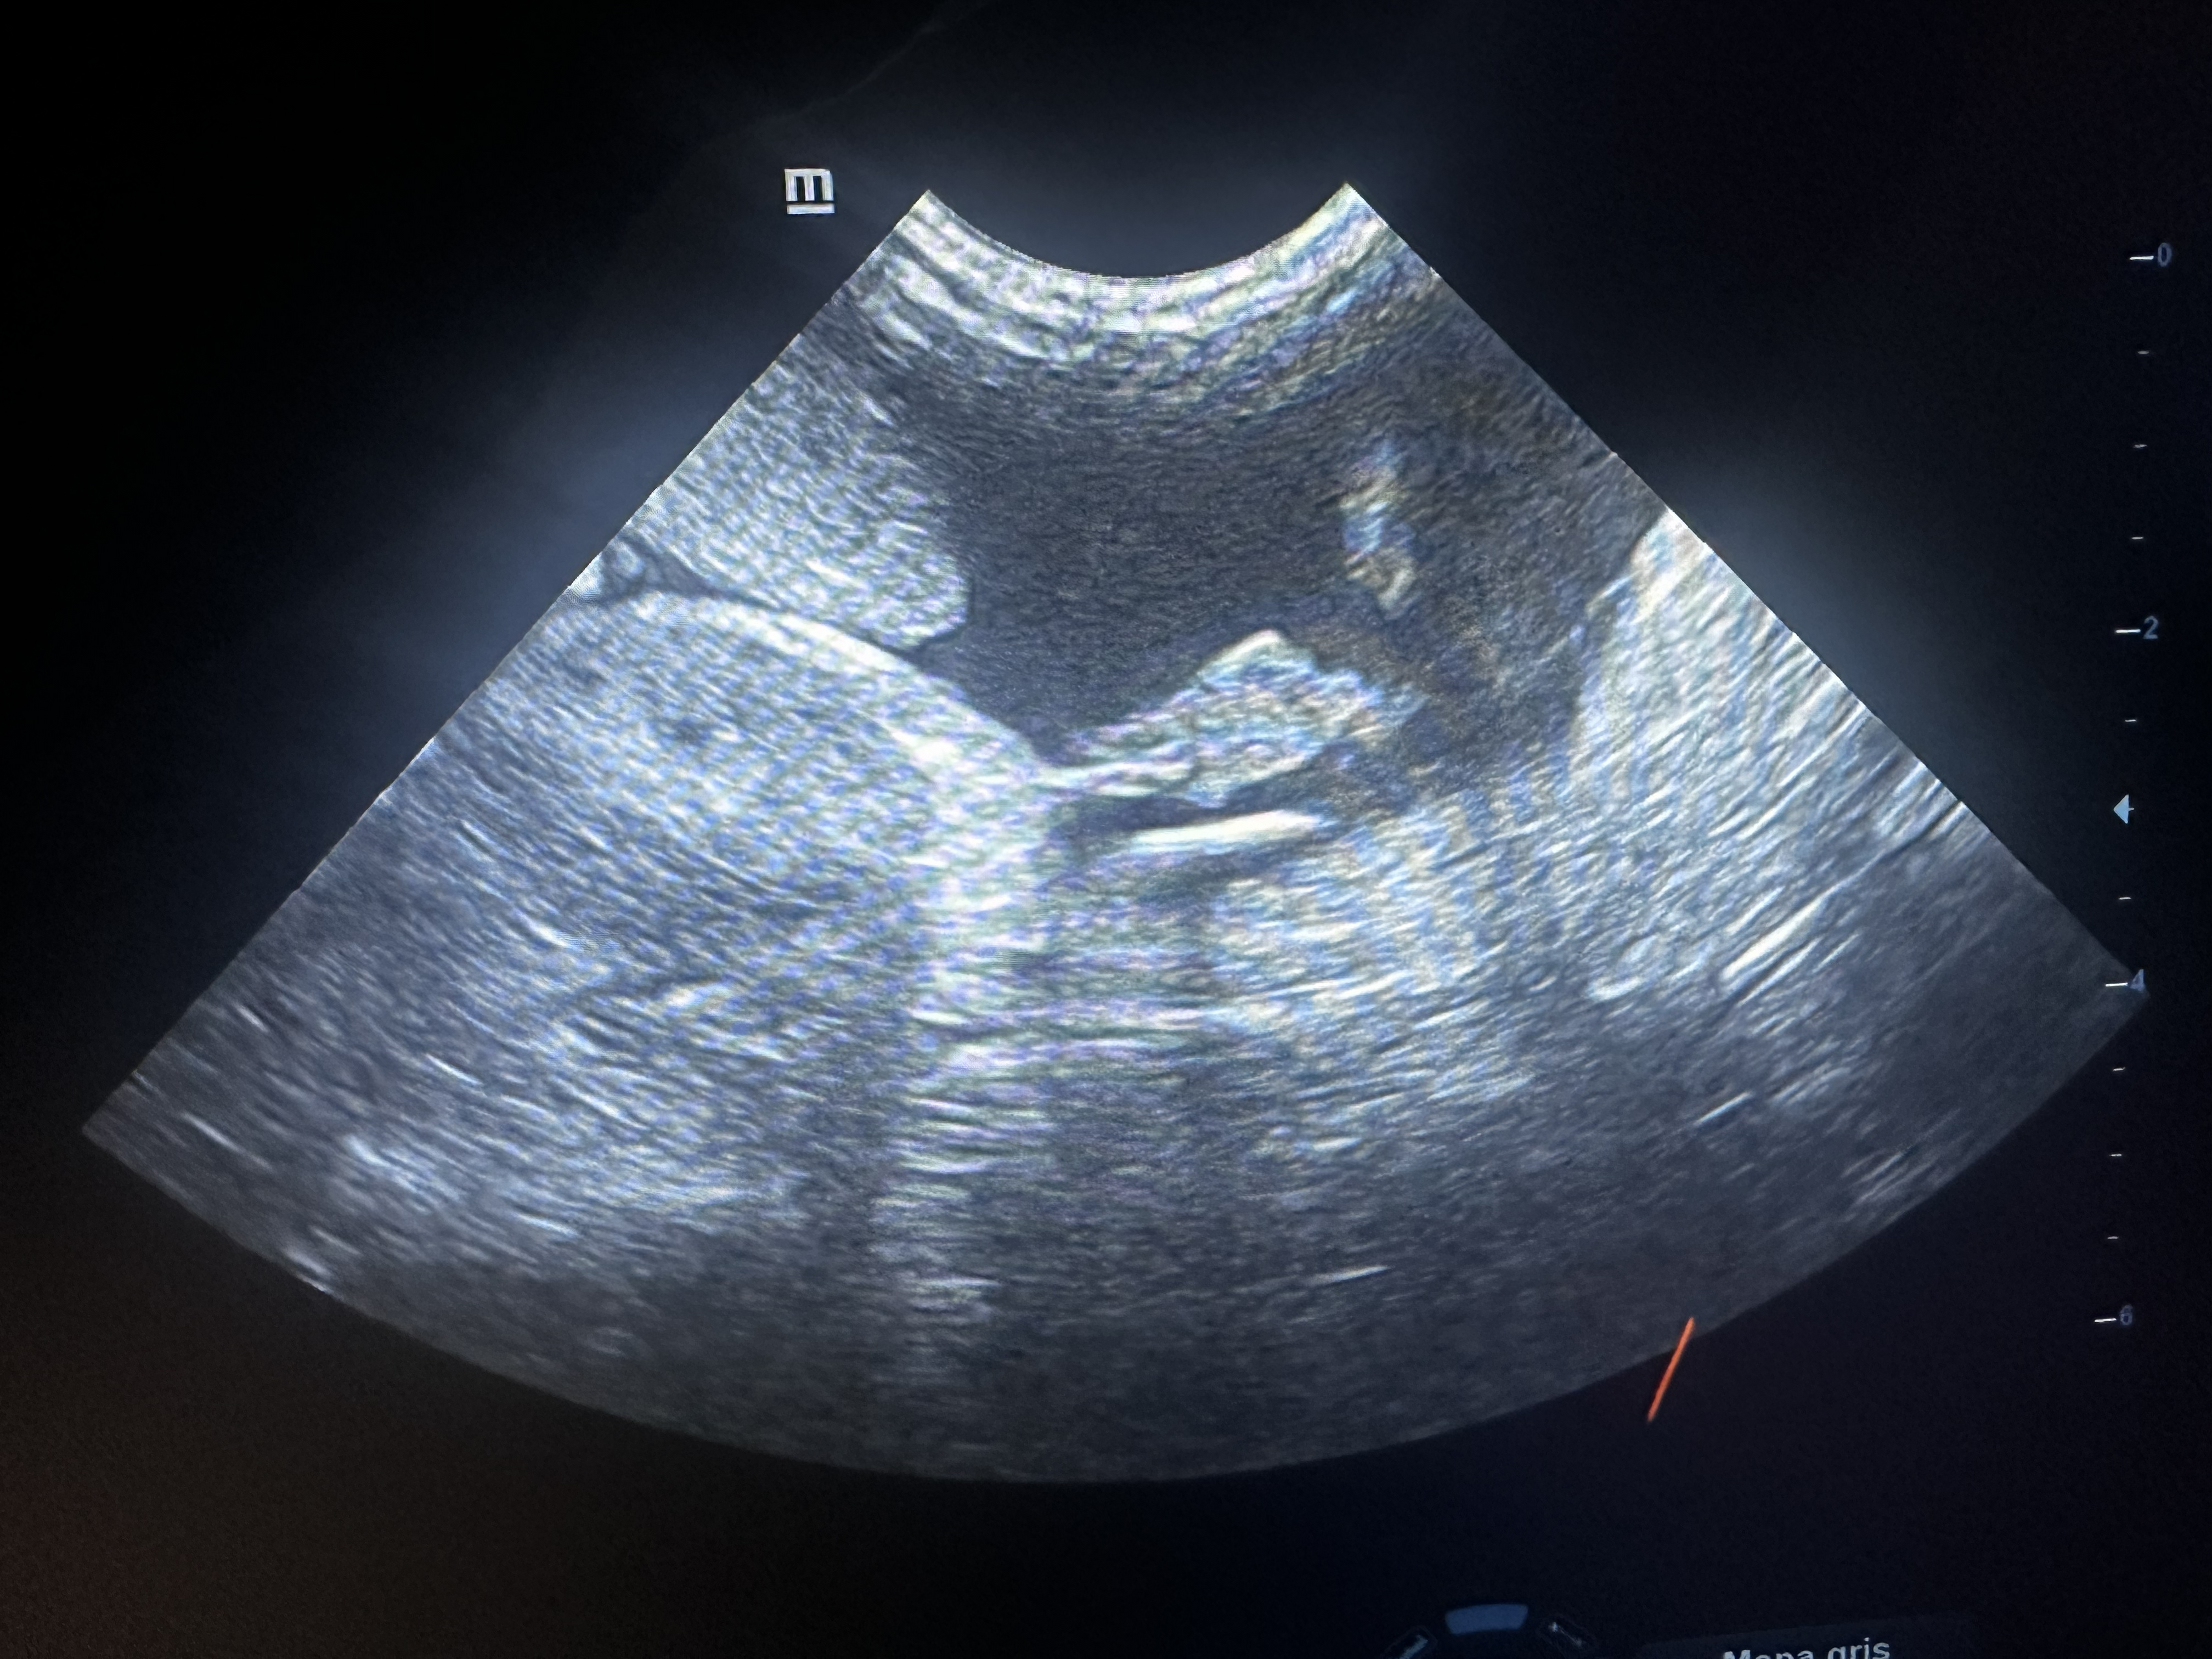

Dentro de CENEV contamos con especialistas dedicados al área de imagenología, dedicados al diagnóstico por pruebas como ultrasonido abdominal, radiología de tórax y abdomen, entre otras.

Nuestros equipos y personal especializado permiten estudios rápidos y de alta calidad para apoyar el diagnóstico clínico.